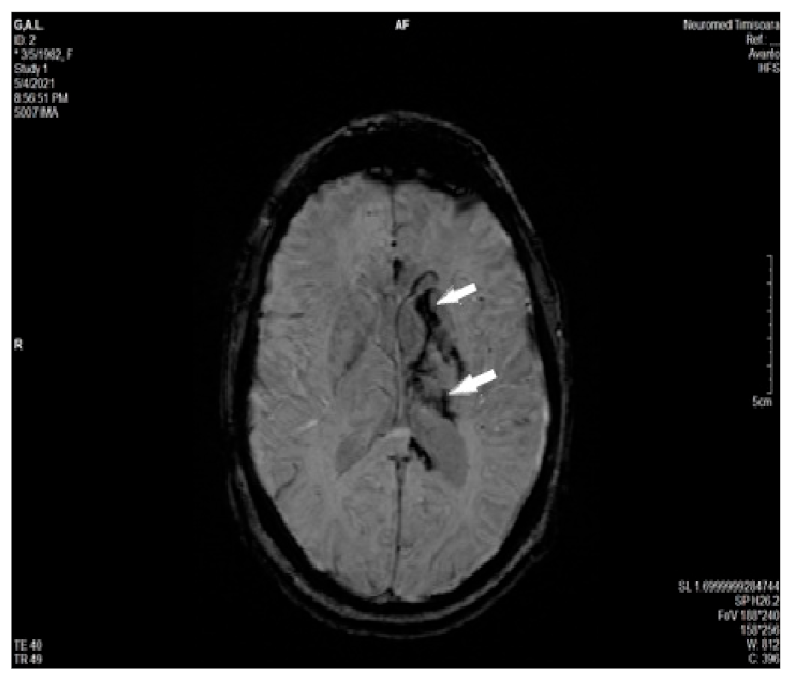

2.2. Imaging